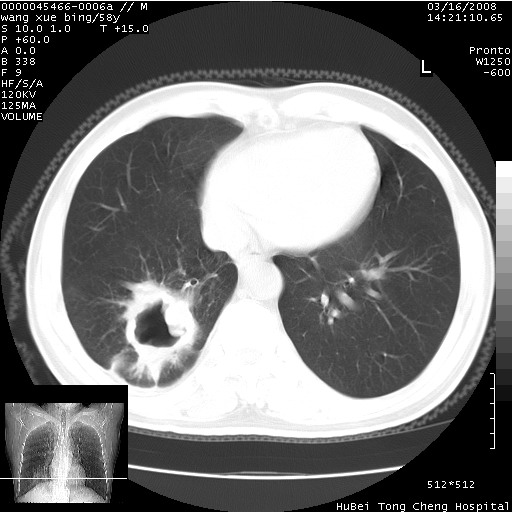

胸部ct轴位平扫(层厚10mm,螺距1.5,重建间隔10mm),图像如下:

右肺下叶团块及不规则空洞,内壁不规则,外缘见粗长毛刺,临近胸膜明显增厚并与病灶关系密切。支持考虑:右肺肺脓肿!建议穿刺病理检查待除外周围型肺癌!

右肺下叶见不规则厚壁空洞,内壁不规则,外缘见粗长毛刺,临近胸膜明显增厚并与病灶关系密切。支持考虑:周围型肺癌!

右肺下叶周围型肺癌伴空洞形成!征象比较明显!分叶、毛刺、胸膜凹陷征、厚壁空洞,壁结节!

空洞壁厚,不规则,其内可见壁结节,周围可见毛刺及阻塞性炎变,多考虑癌性病变.

空洞内壁不规整,有壁结节,周围有毛刺,支持癌性空洞。